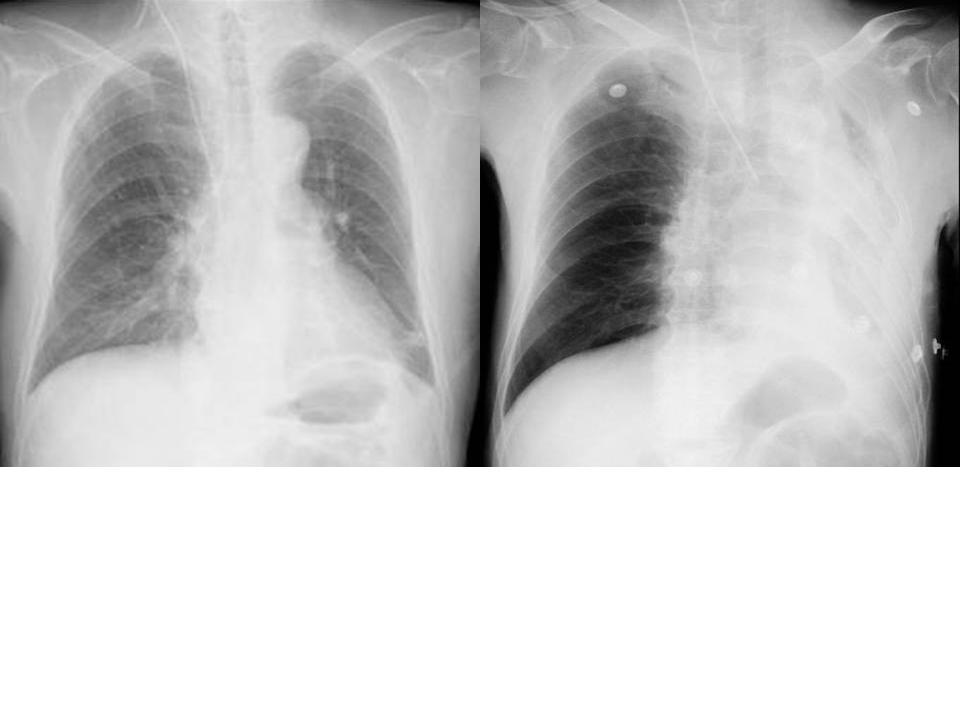

例えば肺の大きさ。

volume

lossや反対に過膨張などの所見は、圧倒的に胸部正面写真がわかりやすいですね。